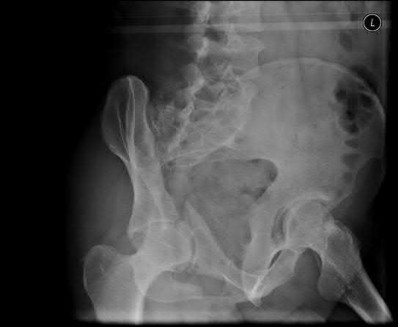

Question 19:

A 50-year-old female presents with sudden onset medial knee pain without mechanical locking. MRI demonstrates a medial meniscus posterior root tear with 4 mm of meniscal extrusion. Biomechanically, untreated meniscal root tears have been shown to be equivalent to which of the following?

Correct Answer: Total meniscectomy

Explanation:

Meniscal root tears completely disrupt the circumferential hoop stresses of the meniscus. Without these intact roots anchoring the meniscus to the tibial plateau, axial loading simply pushes the meniscus out of the joint (extrusion). Biomechanical studies have demonstrated that an untreated meniscal root tear leads to peak contact pressures identical to a total meniscectomy, resulting in rapid joint degeneration.